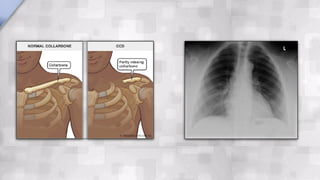

A rare congenital syndrome that has dental significance. Transmission of the condition is by either

parent to a child. CCD can also occur sporadically with no apparent hereditary influence. The

diagnosis is based on the finding of an absence of clavicles.

A rare congenitalsyndrome that has dental significance. Transmission of the condition is by either parent to a child. CCD can also occur sporadically with no apparent hereditary influence. The diagnosis is based on the finding of an absence of clavicles. The development of the dentition is delayed. Complete primary dentition at 15 years of age resulting from delayed resorption of the deciduous teeth and delayed eruption of the permanent teeth is not uncommon. One of the important distinguishing characteristics is the presence of supernumerary teeth.  CLEIDOCRANIAL DYSPLASIA